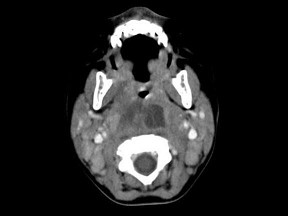

10个月大的婴儿,发热,曾患中耳炎,CT扫描如图所示,正确的描述或诊断是()

A.咽后壁软组织肿胀

B.其内密度不均

C.颈椎骨质未见明显异常

D.咽后壁脓肿

E.咽后壁寒性脓肿

[多选题]10个月大的婴儿,发热,曾患中耳炎,CT扫描如图所示,正确的描述或诊断是()A.咽后壁软组织肿胀B.其内密度不均C.颈椎骨质未见明显异常D.咽后壁脓肿

[多选题] 10个月大的婴儿,发热,曾患中耳炎,CT扫描如图所示,正确的描述或诊断是()A .咽后壁软组织肿胀B .其内密度不均C .颈椎骨质未见明显异常D .咽后壁脓肿E .咽后壁寒性脓肿

[多选题] 10个月大的婴儿,发热,曾患中耳炎,CT扫描如图所示,正确的描述或诊断是()A . 咽后壁软组织肿胀B . 其内密度不均C . 颈椎骨质未见明显异常D . 咽后壁脓肿E . 咽后壁寒性脓肿